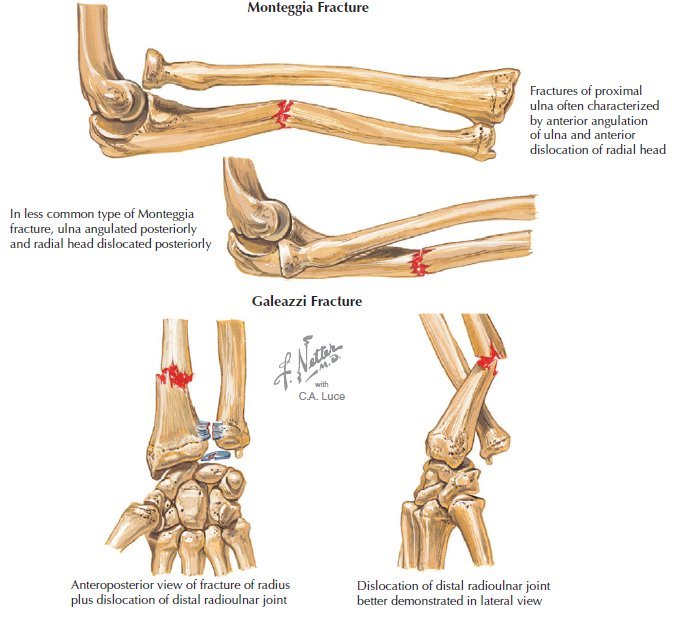

Monteggia fracture. Complications?

Proxima ulna fracture characterized by anterior angulation of ulna and anterior dislocation of radial head Complications: Radial nerve/PIN injury. Compartment syndrome

Galeazzi fracture

Distal 1/3 radial shaft fracture with distal RU dx. May be anterior or posterior.